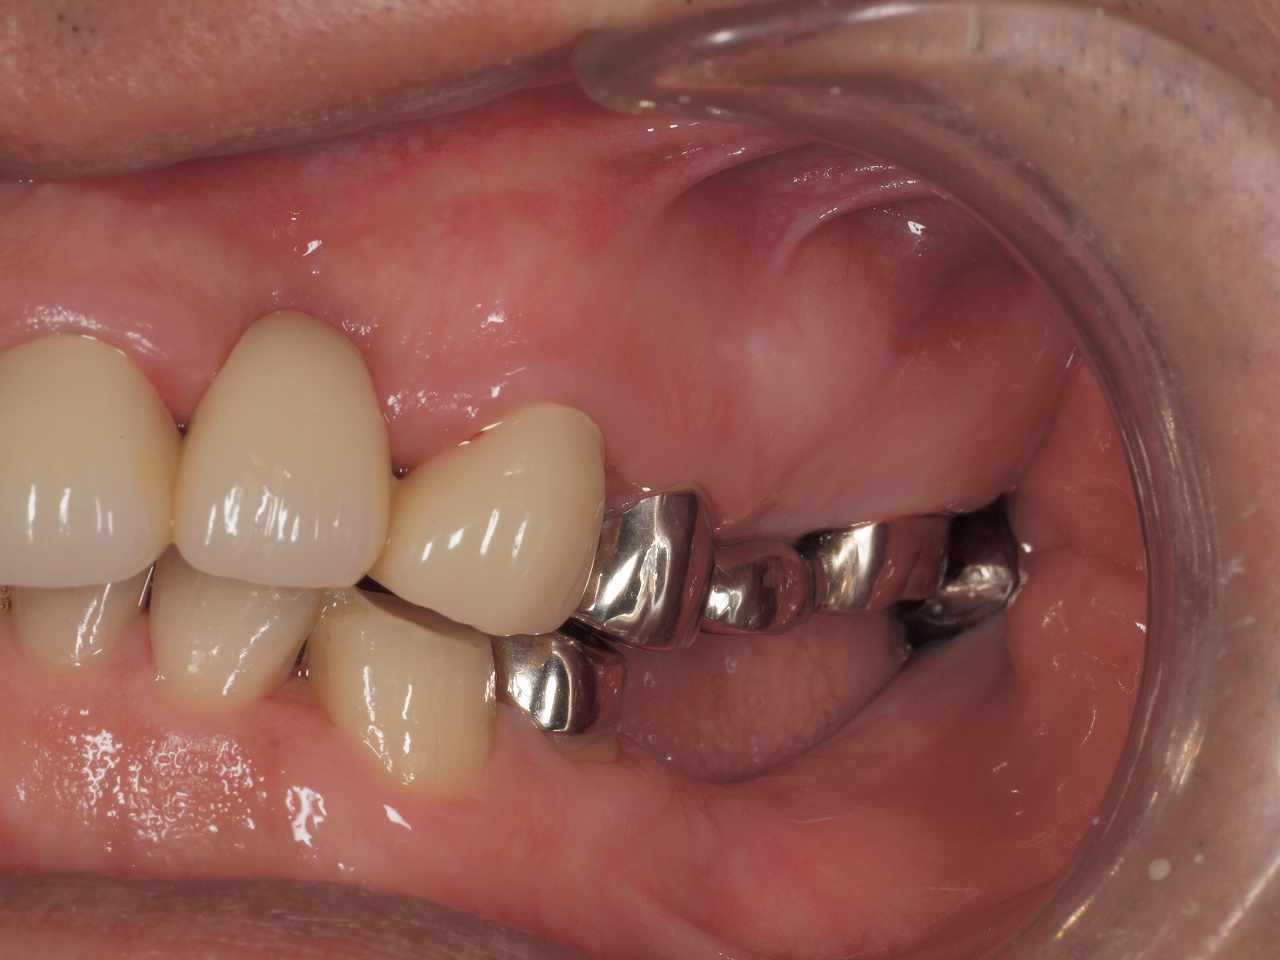

MTMにて歯列矯正を行っていきます。 空隙を詰めていきます。| |広島市安佐南区の歯科医院 MTMにて歯列矯正を行っていきます。 空隙を詰めていきます。 トップ お知らせ・ブログ MTMにて歯列矯正を行っていきます。 空隙を詰めていきます。 MTMにて歯列矯正を行っていきます。 空隙を詰めていきます。 Web診療予約 初めての方へ 選ばれ続ける理由 院内設備について 歯が痛いしみる一般歯科 歯がぐらぐらする歯周病 健康な歯を保ちたい予防歯科 子供の虫歯予防をしたい小児歯科 銀歯をセラミックに審美歯科 白い歯を目指しませんか?ホワイトニング 矯正専門医がいるので安心矯正歯科 抜けた歯を補いたいインプラント・入れ歯 医院案内 スタッフ紹介 メリィハウス歯科クリニックオフィシャルホームページ ラベンダー歯科クリニックオフィシャルホームページ お知らせ・ブログ ホーム 診療科目 一般歯科 歯周病治療 予防治療 小児歯科 審美治療 ホワイトニング 矯正歯科 入れ歯・インプラント マウスピース矯正 初めての方へ 院長・スタッフ 設備紹介 医院案内・アクセス メニューを閉じる